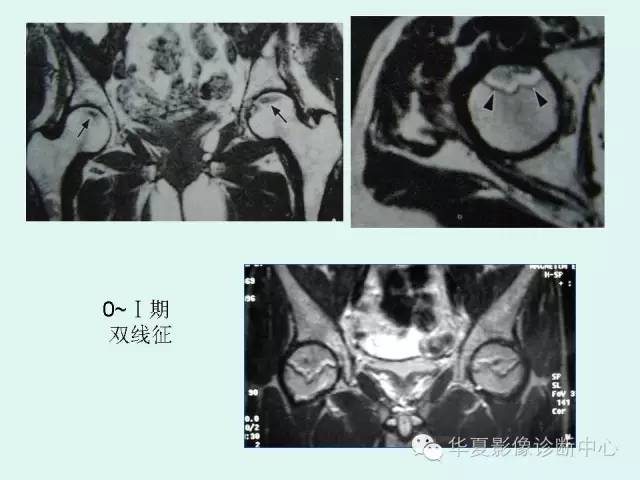

【PPT】股骨头缺血性坏死